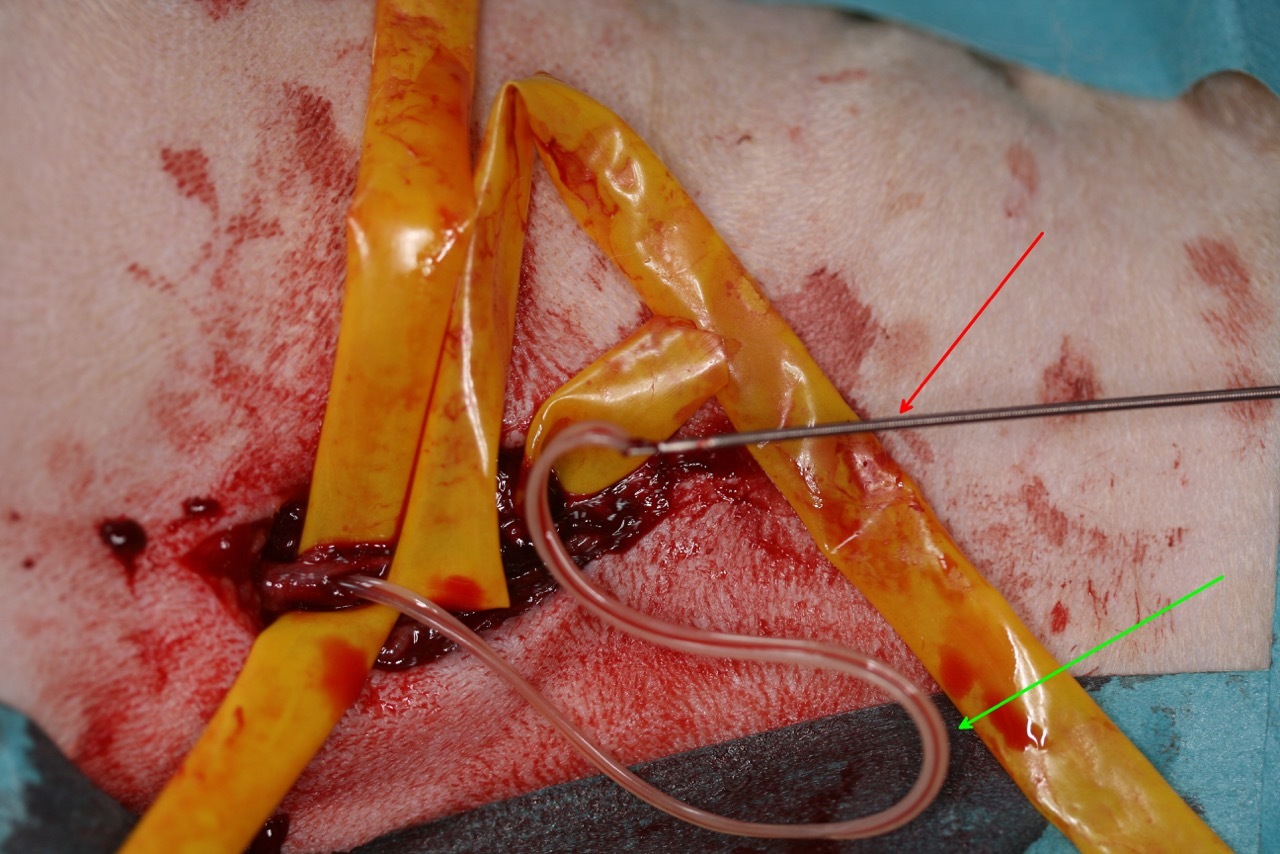

Für Quax begann nun eine mehrmonatige Therapie. Im ersten Schritt wurde er mit einem Herzmedikament zur Unterstützung der Funktion des angegriffenen Herzens, einem Antibiotikum gegen bestimmte Keime, die gerne in den Herzwürmern leben und den Hund zusätzlich gefährden können und einem Kortison zur Eindämmung entzündlich-allergischer Reaktionen versorgt. Auch wenn sich Quax daraufhin bereits deutlich besser fühlte, musste er unbedingt strikt ruhig gehalten werden. Es folgte dann die chirurgische Entfernung der Herzwürmer aus dem Rechtsherz und, soweit erreichbar, aus den großen Lungenarterien. Dieser Schritt war notwendig, da das medikamentöse Abtöten einer so großen Wurmbürde ein zu großes Risiko für das Leben des Hundes darstellen würde. Unter lokaler Betäubung wurde über einen kleinen Hautschnitt die große Halsvene dargestellt, Mit einer langen, flexiblen Fremdkörperzange wurden die Würmer aus dem Herzen entfernt. Quax überstand diesen Eingriff mit Bravour.